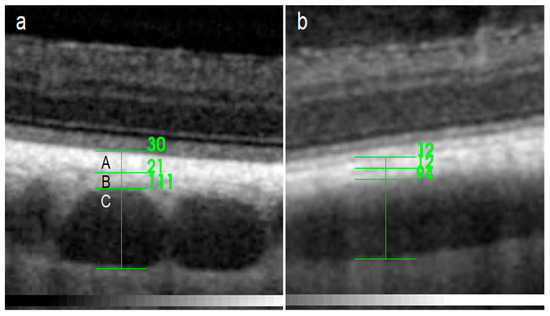

| RPE-BmCc | MSVL | LVLS | WCT | |

|---|---|---|---|---|

| D | ||||

| MA | 28.7 ± 7.49 | 32.59 ± 7.83 | 121.72 ± 24.58 | 183.02 ± 30.15 |

| SN | 26.44 ± 5.04 | 31.62 ± 7.62 | 124.87 ± 28.32 | 182.93 ± 32.01 |

| V | ||||

| MA | 7.71 ± 0.96 | 24.43 ± 8.07 | 78.21 ± 19.22 | 110.24 ± 23.50 |

| SN | 8.13 ± 0.50 | 24.33 ± 6.21 | 75.39 ± 14.28 | 107.84 ± 17.68 |

| TempT | ||||

| MA | 10.76 ± 2.17 | 38.15 ± 7.64 | 126.78 ± 35.78 | 175.69 ± 38.58 |

| SN | 10.90 ± 2.38 | 45.43 ± 10.29 | 125.67 ± 19.96 | 182.00 ± 23.54 |

| TempNT | ||||

| MA | 8.12 ± 0.91 | 27.11 ± 9.87 | 84.45 ± 17.24 | 119.68 ± 24.81 |

| SN | 8.25 ± 0.68 | 30.86 ± 6.94 | 99.59 ± 22.98 | 138.62 ± 26.81 |

| NasT | ||||

| MA | 9.83 ± 1.43 | 32.90 ± 10.02 | 96.78 ± 12.56 | 139.52 ± 15.67 |

| SN | 9.33 ± 1.47 | 33.03 ± 5.40 | 102.33 ± 24.48 | 144.69 ± 24.06 |

| NasNT | ||||

| MA | 8.05 ± 0.86 | 26.34 ± 8.90 | 89.72 ± 14.19 | 124.12 ± 19.40 |

| SN | 8.44 ± 0.69 | 29.74 ± 7.50 | 90.59 ± 12.43 | 128.77 ± 16.89 |